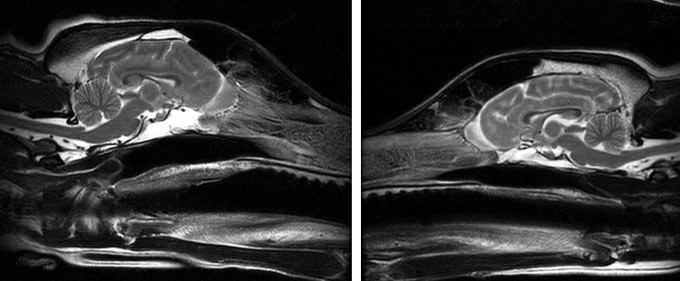

Scans from 33 dog breeds revealed variation in brain regions involved in scent hunting, guarding and companionship.

debbiehelbing/iStock /Getty Images Plus